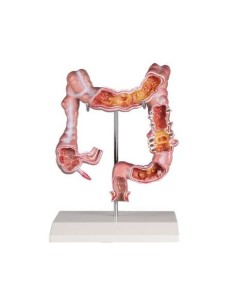

Scopri il Mondo dell’Anatomia con Modelli anatomici di Precisione

Modelli Anatomici Dettagliati per Ogni Necessità

Dal cranio in 22 parti con incastri magnetici ai modelli di colonna vertebrale, da quelli di articolazioni a quelli di cuore, ogni pezzo della nostra collezione è progettato per un’immersione totale nello studio dell’anatomia umana. I nostri modelli, realizzati tramite scansioni di ossa vere, garantiscono un’esperienza tattile autentica e una fedeltà di peso quasi identica agli originali.

Strumenti Didattici Innovativi per l’Educazione e la Pratica Medica

Essenziali per studenti e professionisti, i nostri modelli anatomici sono strumenti didattici che permettono di osservare le strutture anatomiche con precisione, eliminando la necessità di dissezioni o studi invasivi. Sono inoltre utili per spiegare ai pazienti le patologie, rendendo la comunicazione più efficace e risparmiando tempo prezioso.